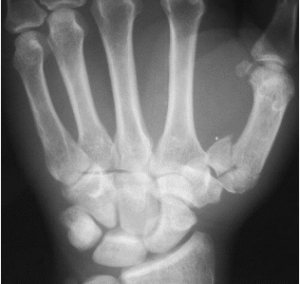

Xquang (thẳng, nghiêng): Đường thấu quang nền xương bàn ngón tay cái (chữ Y hoặc chữ T)